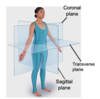

Name the cross-sections

midsagittal

along midline

parasagittal

not along midline